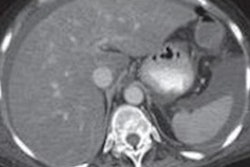

MR image of a child’s liver with severe NAFLD. The liver is 38% fat, compared with a normal level of 1%. Image courtesy of UCSD School of Medicine.Using threshold values of 0.69 to 0.82 to distinguish between no fat concentration and mild fat concentration in the liver, the MRI-estimated liver proton density fat fraction was able to predict the histologic degree of fat concentration with an overall accuracy of 56%.